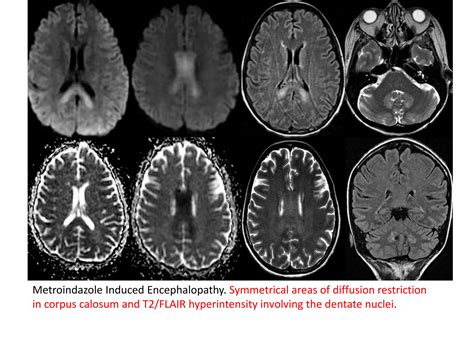

• Exogenous Toxicity: The intake of certain drugs, polypharmacy interactions, illicit substances, or exposure to environmental toxins such as heavy metals or carbon monoxide can induce an encephalopathic state.

• toxic metabolic encephalopathy radiology